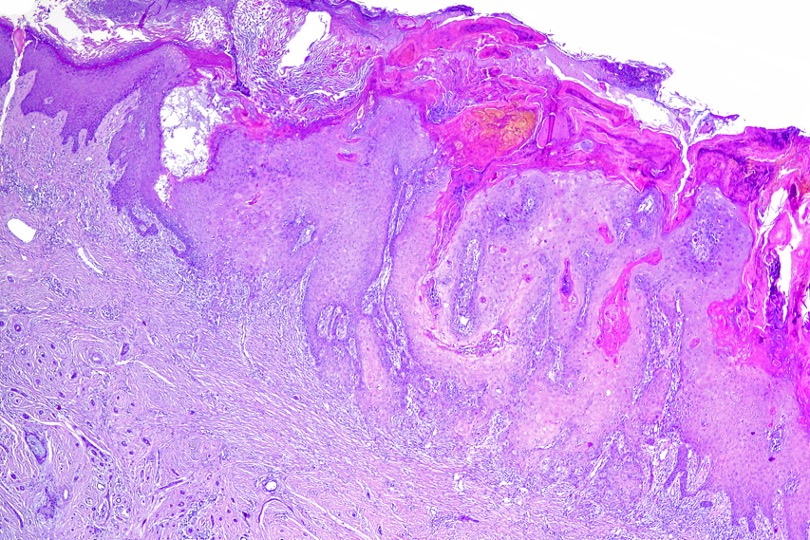

Histological features

•Hamartoma characterized by abnormalities of epidermis, hair follicles, sebaceous glands, apocrine sweat glands & connective tissue

•Epidermis often papillomatous

•High, increased hyperplastic, sebaceous glands with openings onto the surface epithelium (in. old lesions, they may be absent)